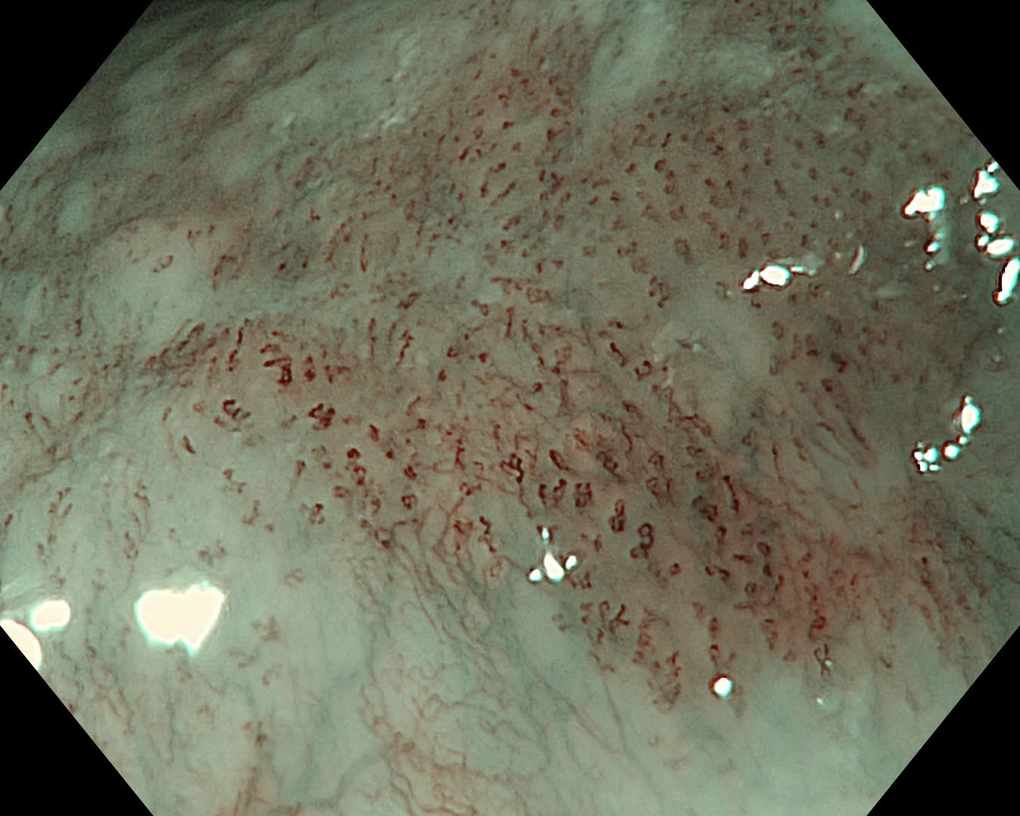

Khi sử dụng NBI, bác sĩ phát hiện một tổn thương phẳng, bắt màu nâu, kích thước khoảng 15mm. Tiếp đó, bác sĩ sử dụng hệ thống Olympus X1 và dây soi EZ1500 (độ phóng đại lên đến 150 lần) cho phép quan sát rõ vi mạch bề mặt.

“Đánh giá vòng mạch nhú nội biểu mô (IPCL) cho thấy đây là type B1 theo phân loại JES, gợi ý ung thư biểu mô vảy thực quản giai đoạn sớm ở lớp niêm mạc, có chỉ định điều trị bằng cắt tách dưới niêm mạc qua nội soi (ESD).

Tổn thương thực quản của bệnh nhân được nhuộm màu, phóng đại rất dễ quan sát (Ảnh: Bệnh viện cung cấp).

Vì thế, việc sử dụng nội soi nhuộm màu phóng đại lên tới 150 lần, giúp hình ảnh sắc nét, hiển thị rõ tổn thương dù là nhỏ nhất, giúp phân tích rõ ràng vi cấu trúc và vi mạch máu của tổn thương, đưa ra nhận định chính xác về tính chất tế bào học của tổn thương, phân biệt tổn thương ung thư và không ung thư từ đó đưa ra hướng can thiệp kịp thời cho người bệnh.